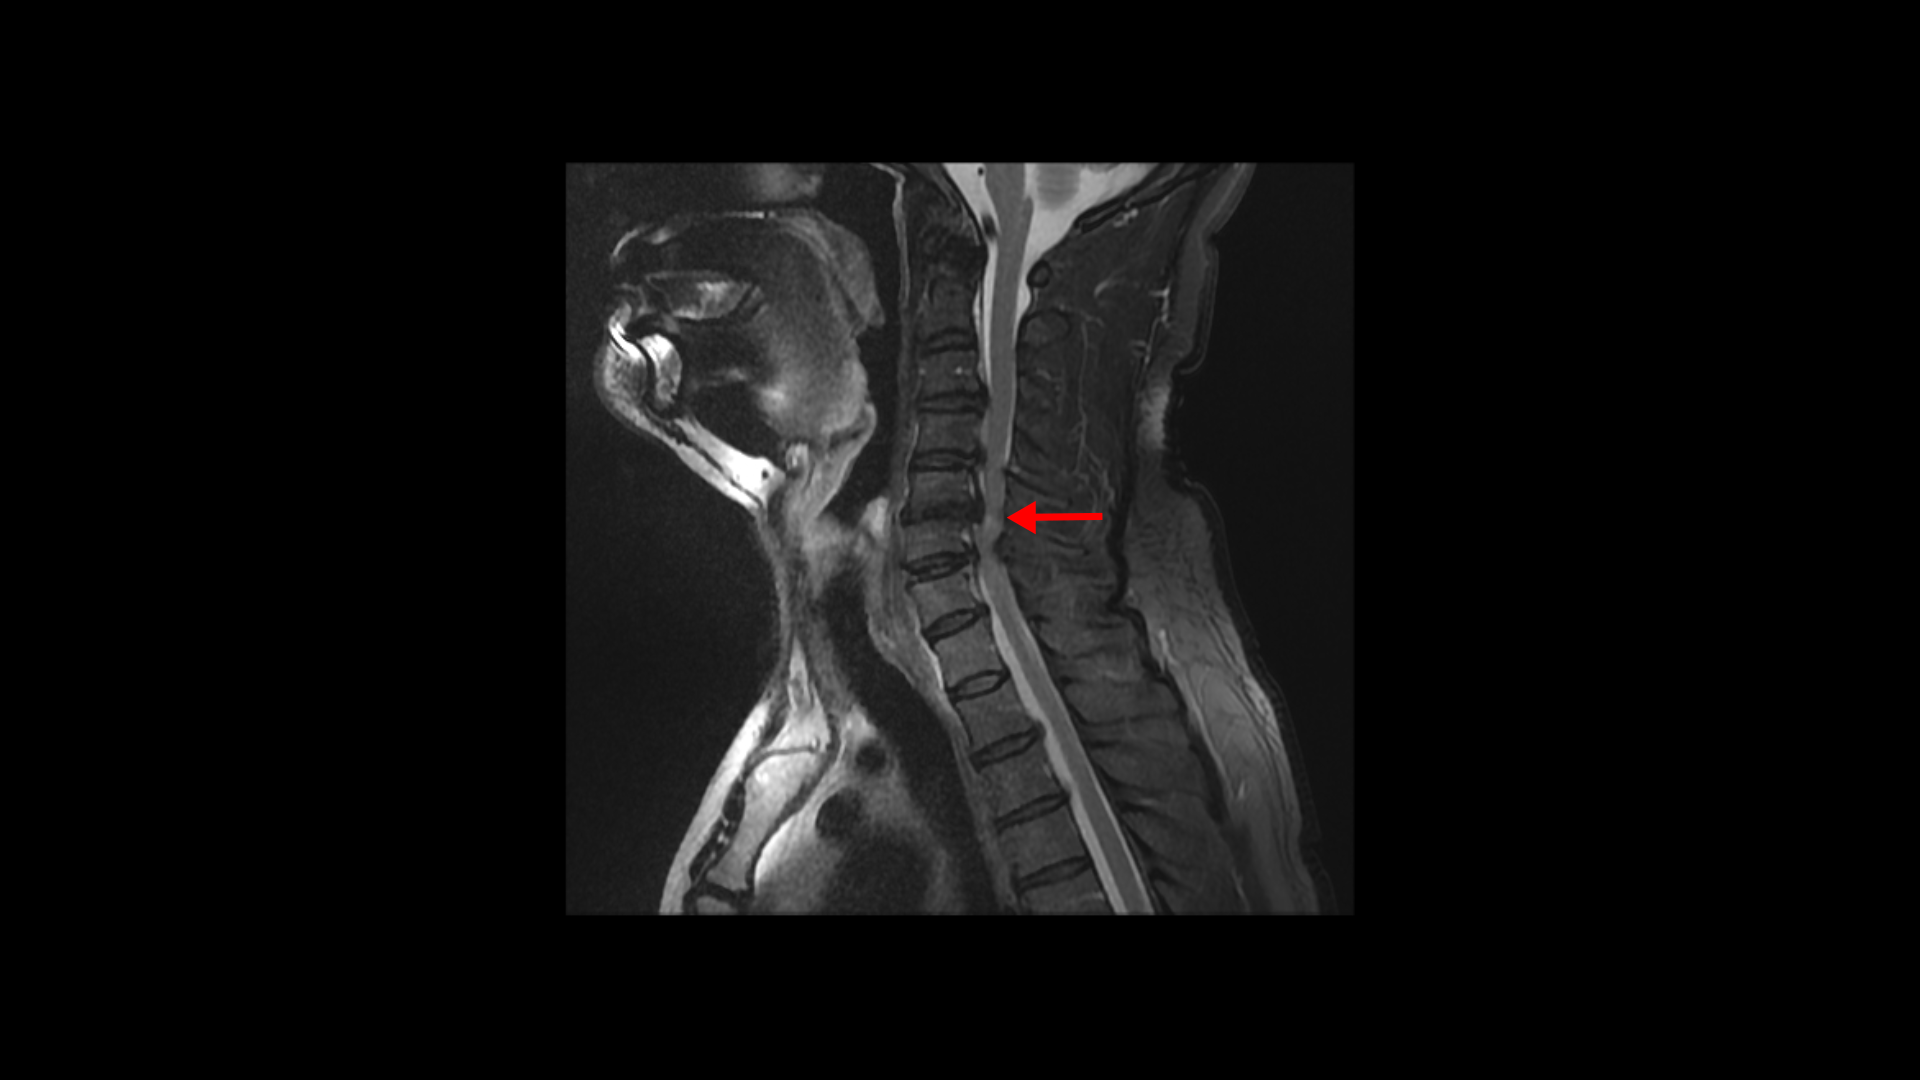

5번 6번 문제가 제일 심각한데, 가운데 우측으로 목디스크 파열이 심하게 있습니다.

오른쪽으로 보시다시피 신경 나가는 길이 디스크와 협착으로 많이 막혀 있고 척수 신경에는 경추척수증, 즉 척수신경의 손상이 보입니다.